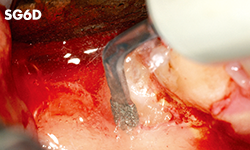

Avulsión de las muelas del juicio y de dientes impactados

Injerto en el seno